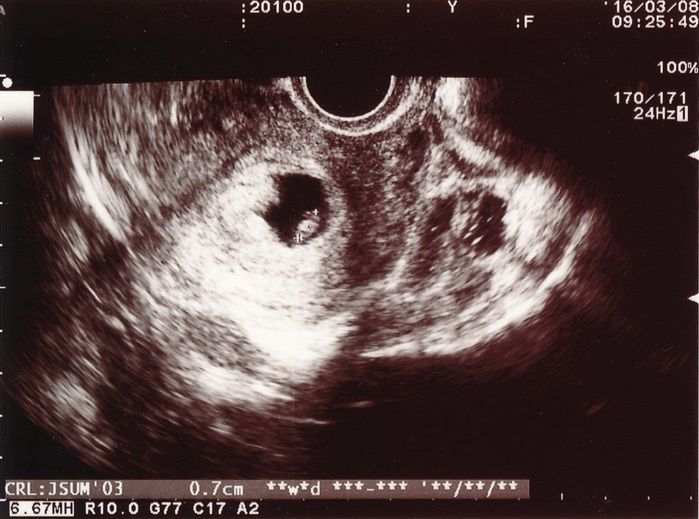

妊娠6週目のエコー写真

待ちに待った診察の日です。自分の中では妊娠していると確信がありましたが、医師のお墨付きをもらわなければなりません。先週よりも大きくなった胎嚢の中に赤ちゃんの姿が見えます。このときは0.7cmですが、心音が確認できたことが決め手となり妊娠が確定しました。しかし、妊娠初期での流産リスクは25%と告げられ、落ち込む暇もなくどのようにして乗り切るかを考え始めました。